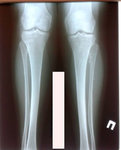

Диагноз: вальгусная деформация голеней (Х - образная)

Дата операции - 16.07.2019г.

[b][color=#FF0000]Диагноз:[/color][/b] [b][i][color=#0000FF]вальгусная деформация голеней (Х - образная)[/color][/i][/b]

[b][color=#FF0000]Дата операции - 16.07.2019г.[/color][/b]